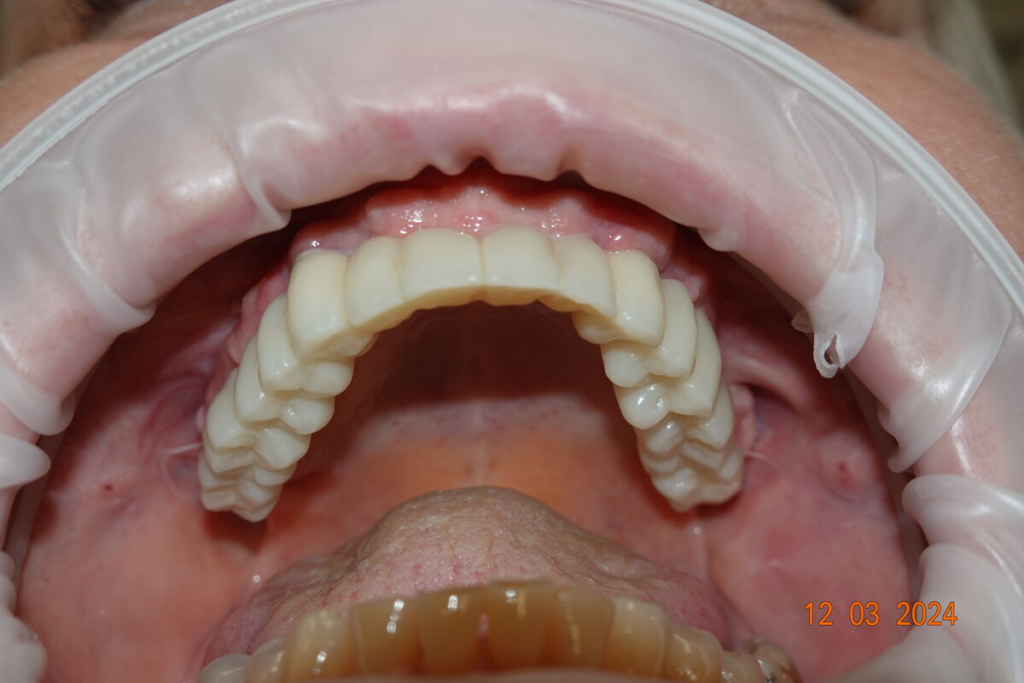

3. Nové zuby tentýž den

Odcházíte s pevnými dočasnými zuby — bez snímatelné protézy.

Můžete mluvit, smát se a jíst měkkou stravu.

Technika All-on-X — I. fáze